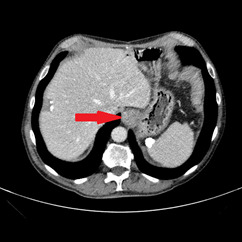

An abdominal ultrasound showed no signs of cholecystitis. A computed tomography (CT) scan revealed dilatation of the intrahepatic and extrahepatic bile duct as well as enlargement of the pancreatic head with ill-defined margins. Following hospitalization, an endoscopic sphincterotomy and endoscopic retrograde biliary drainage with 8.5 fr × 9 mm plastic stent were performed. The brush cytology of the common bile duct performed during the ERCP (endoscopic retrograde cholangiopancreatography) was positive for adenocarcinoma type malignant cells whose cytomorphological and immunophenotypic aspects were compatible with biliopancreatic primary. A magnetic resonance imaging (MRI) scan showed a 2 cm hypointense mass in the pancreatic head, with no signs of invasion in the main blood vessels (Figure 1).